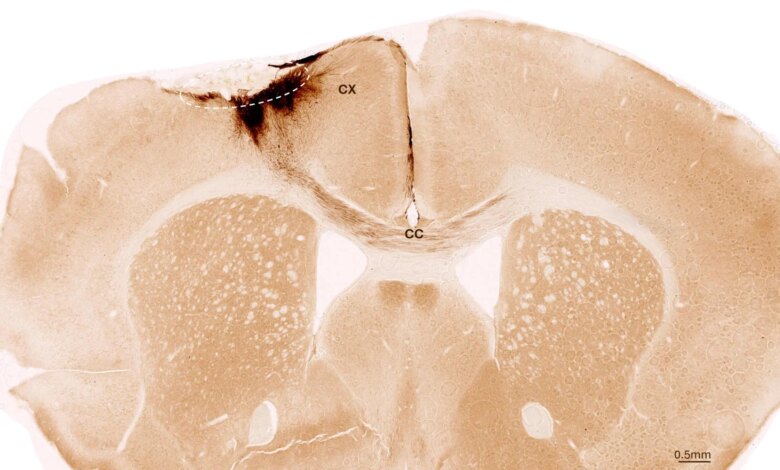

استخدمت الدراسات الخلايا الجذعية العصبية البشرية ، والتي يمكن أن تتشكل منها أنواع خلايا مختلفة من الجهاز العصبي. تم اشتقاق الخلايا الجذعية من الخلايا الجذعية القادمة المستحثة ، والتي بدورها يمكن تصنيعها من الخلايا الجسدية البشرية الطبيعية. من أجل تحقيقهم ، تسبب الباحثون في حدوث سكتة دماغية دائمة في الفئران ، والتي تشبه الخصائص عن كثب مظهر من مظاهر السكتة الدماغية عند البشر. تم تعديل الحيوانات وراثيا حتى لا ترفض الخلايا الجذعية البشرية.

بعد أسبوع واحد من تحريض السكتة الدماغية ، قام فريق البحث بزراعة الخلايا الجذعية العصبية في منطقة الدماغ المصابة ولاحظ التطورات اللاحقة باستخدام مجموعة متنوعة من الأساليب الكيميائية الحيوية. يقول Tackenberg: “لقد وجدنا أن الخلايا الجذعية قد نجت لفترة التحليل الكاملة لمدة خمسة أسابيع وأن معظمها تحول إلى خلايا عصبية ، والتي تواصلت في الواقع مع خلايا الدماغ الموجودة بالفعل”.